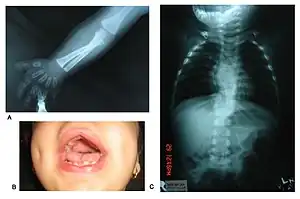

Robinow noted the resemblance of affected patients' faces to that of a fetus, using the term "fetal facies" to describe the appearance of a small face and widely spaced eyes.[1] Clinical features also may include a short, upturned nose, a prominent forehead, and a flat nasal bridge. The upper lip may be "tented",[1] exposing dental crowding, "tongue tie", or gum hypertrophy.

Though the eyes do not protrude, abnormalities in the lower eyelid may give that impression. Surgery may be necessary if the eyes cannot close fully. In addition, the ears may be set low on the head or have a deformed pinna.[1]

Patients suffer from dwarfism, short lower arms, small feet, and small hands. Fingers and toes may also be abnormally short and laterally or medially bent. The thumb may be displaced and some patients, notably in Turkey, experience ectrodactyly.[1] All patients often suffer from vertebral segmentation abnormalities. Those with the dominant variant have, at most, a single butterfly vertebra.[2] Those with the recessive form, however, may suffer from hemivertebrae, vertebral fusion, and rib anomalies. Some cases resemble Jarcho-Levin syndrome or spondylocostal dysostosis.[1]